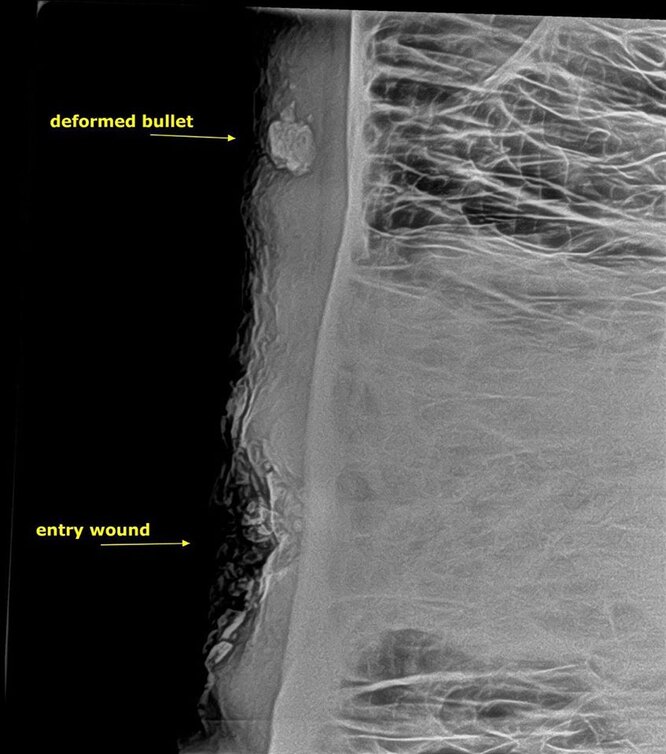

На місце була викликана бригада ветеринарів, які приспали слона, вистріливши в нього дротиком із транквілізатором. Переносний рентген-апарат допоміг фахівцям оцінити ситуацію.

Одним із найскладніших етапів стало вилучення кулі, яка міцно засіла у кістці. Коли її вдалося дістати, рану продезінфікували та зашили. Ветеринари дочекалися пробудження слона, щоб переконатися, що тварина в порядку.